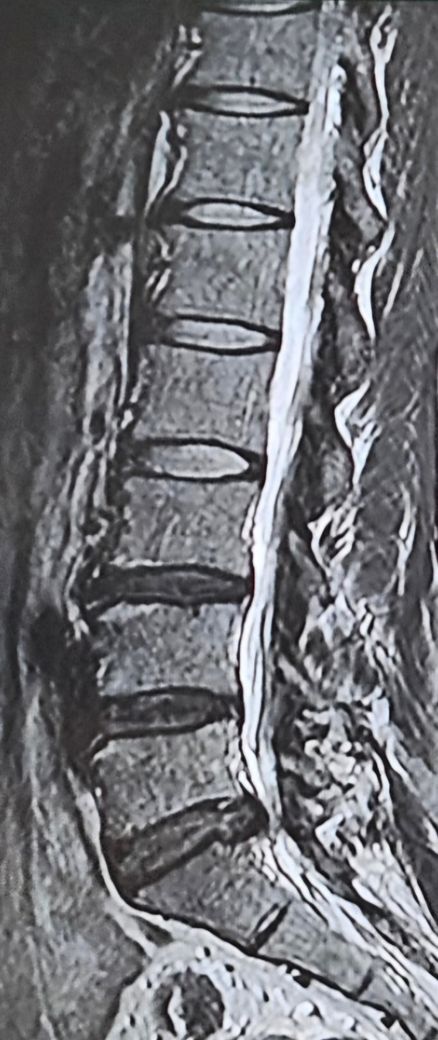

• 2번 째 사진

위 사진을 봤을때 약간의 찢어짐은 있지만 상태가 심각해보이지는 않습니다 보통 퇴행성 디스크는 마모되거나 탈수되어 두께가 줄어들고 추간판탈출증(허리디스크)는 내핵이 바깥으로 밀려나와 신경을 압박하는 상태입니다 이는 위와같은 다리통증이나 저림이 나타납니다 그래서 추간판 탈출증의 증상으로보입니다

보통은 위의 대답처럼 디스크의 내핵이 바깥으로 밀려나와 신경을 압박하는상태인데 그것은 시간이 지나면 자연스럽게 밀려나온게 제자리로 돌아갑니다

가벼운 걷기운동과 통증이 심할때 주사치료를 통해서 시간을 좀 보내시면 자연스럽게 디스크가 제자리로 돌아가 증상이 호전될 가능성이 높습니다 수술을 아직은 하지마시고 통증이 너무 심해지면 다시 병원에 방문해서 상담해보시는것을 권해드립니다

디스크의 섬유륜이 찢어졌고 아주 가벼운 탈출이 있는 상태입니다.

이렇게 요추전만을 실천하면서 생활하시다보면 천천히 찢어진 디스크가 아물고 방사통 및 허리 통증이 모두 없어지실겁니다.